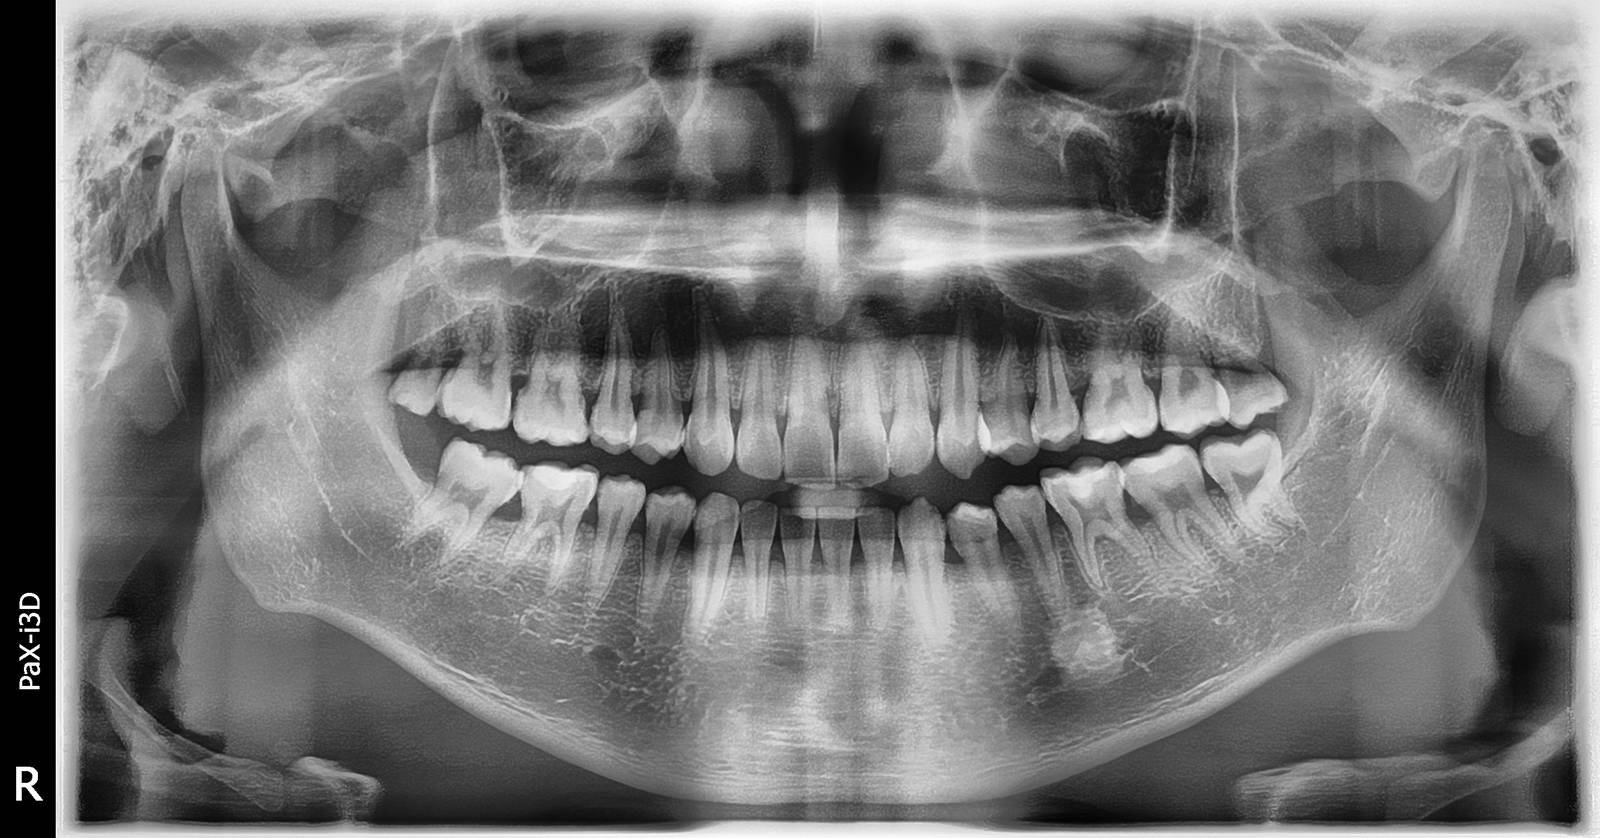

口腔全景片到底有什么用???